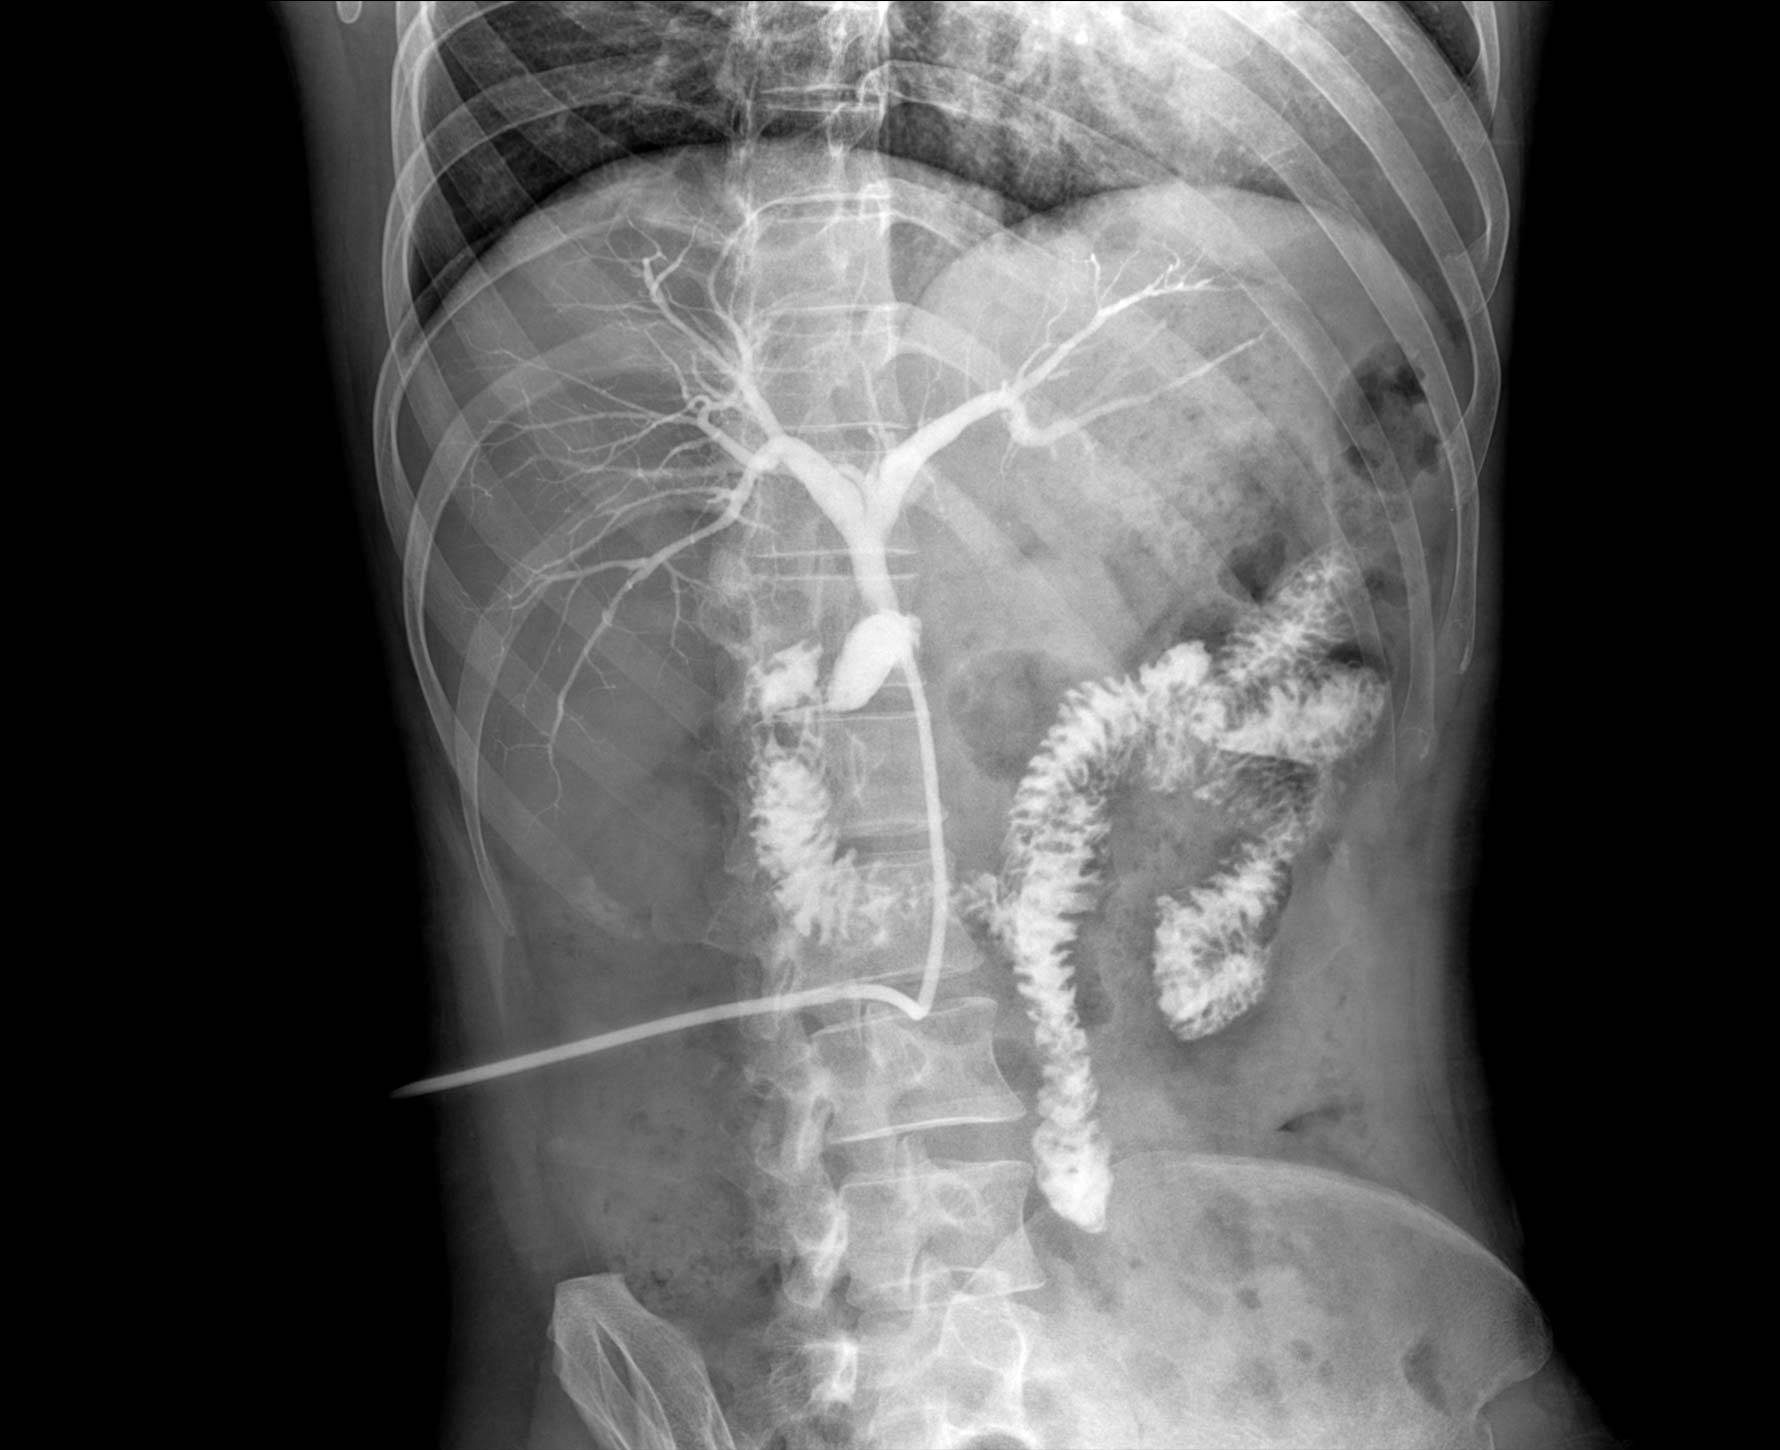

临床图像